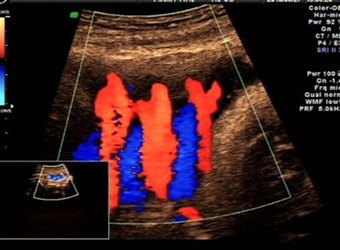

怀孕以后的孕麻麻,几乎每个月都要做不同的检查,做完B超后,很多孕麻麻发现B超单上有双肾未见明显分离的结论,那么双肾未分离是什么意思,更有一些网妈拿双肾…